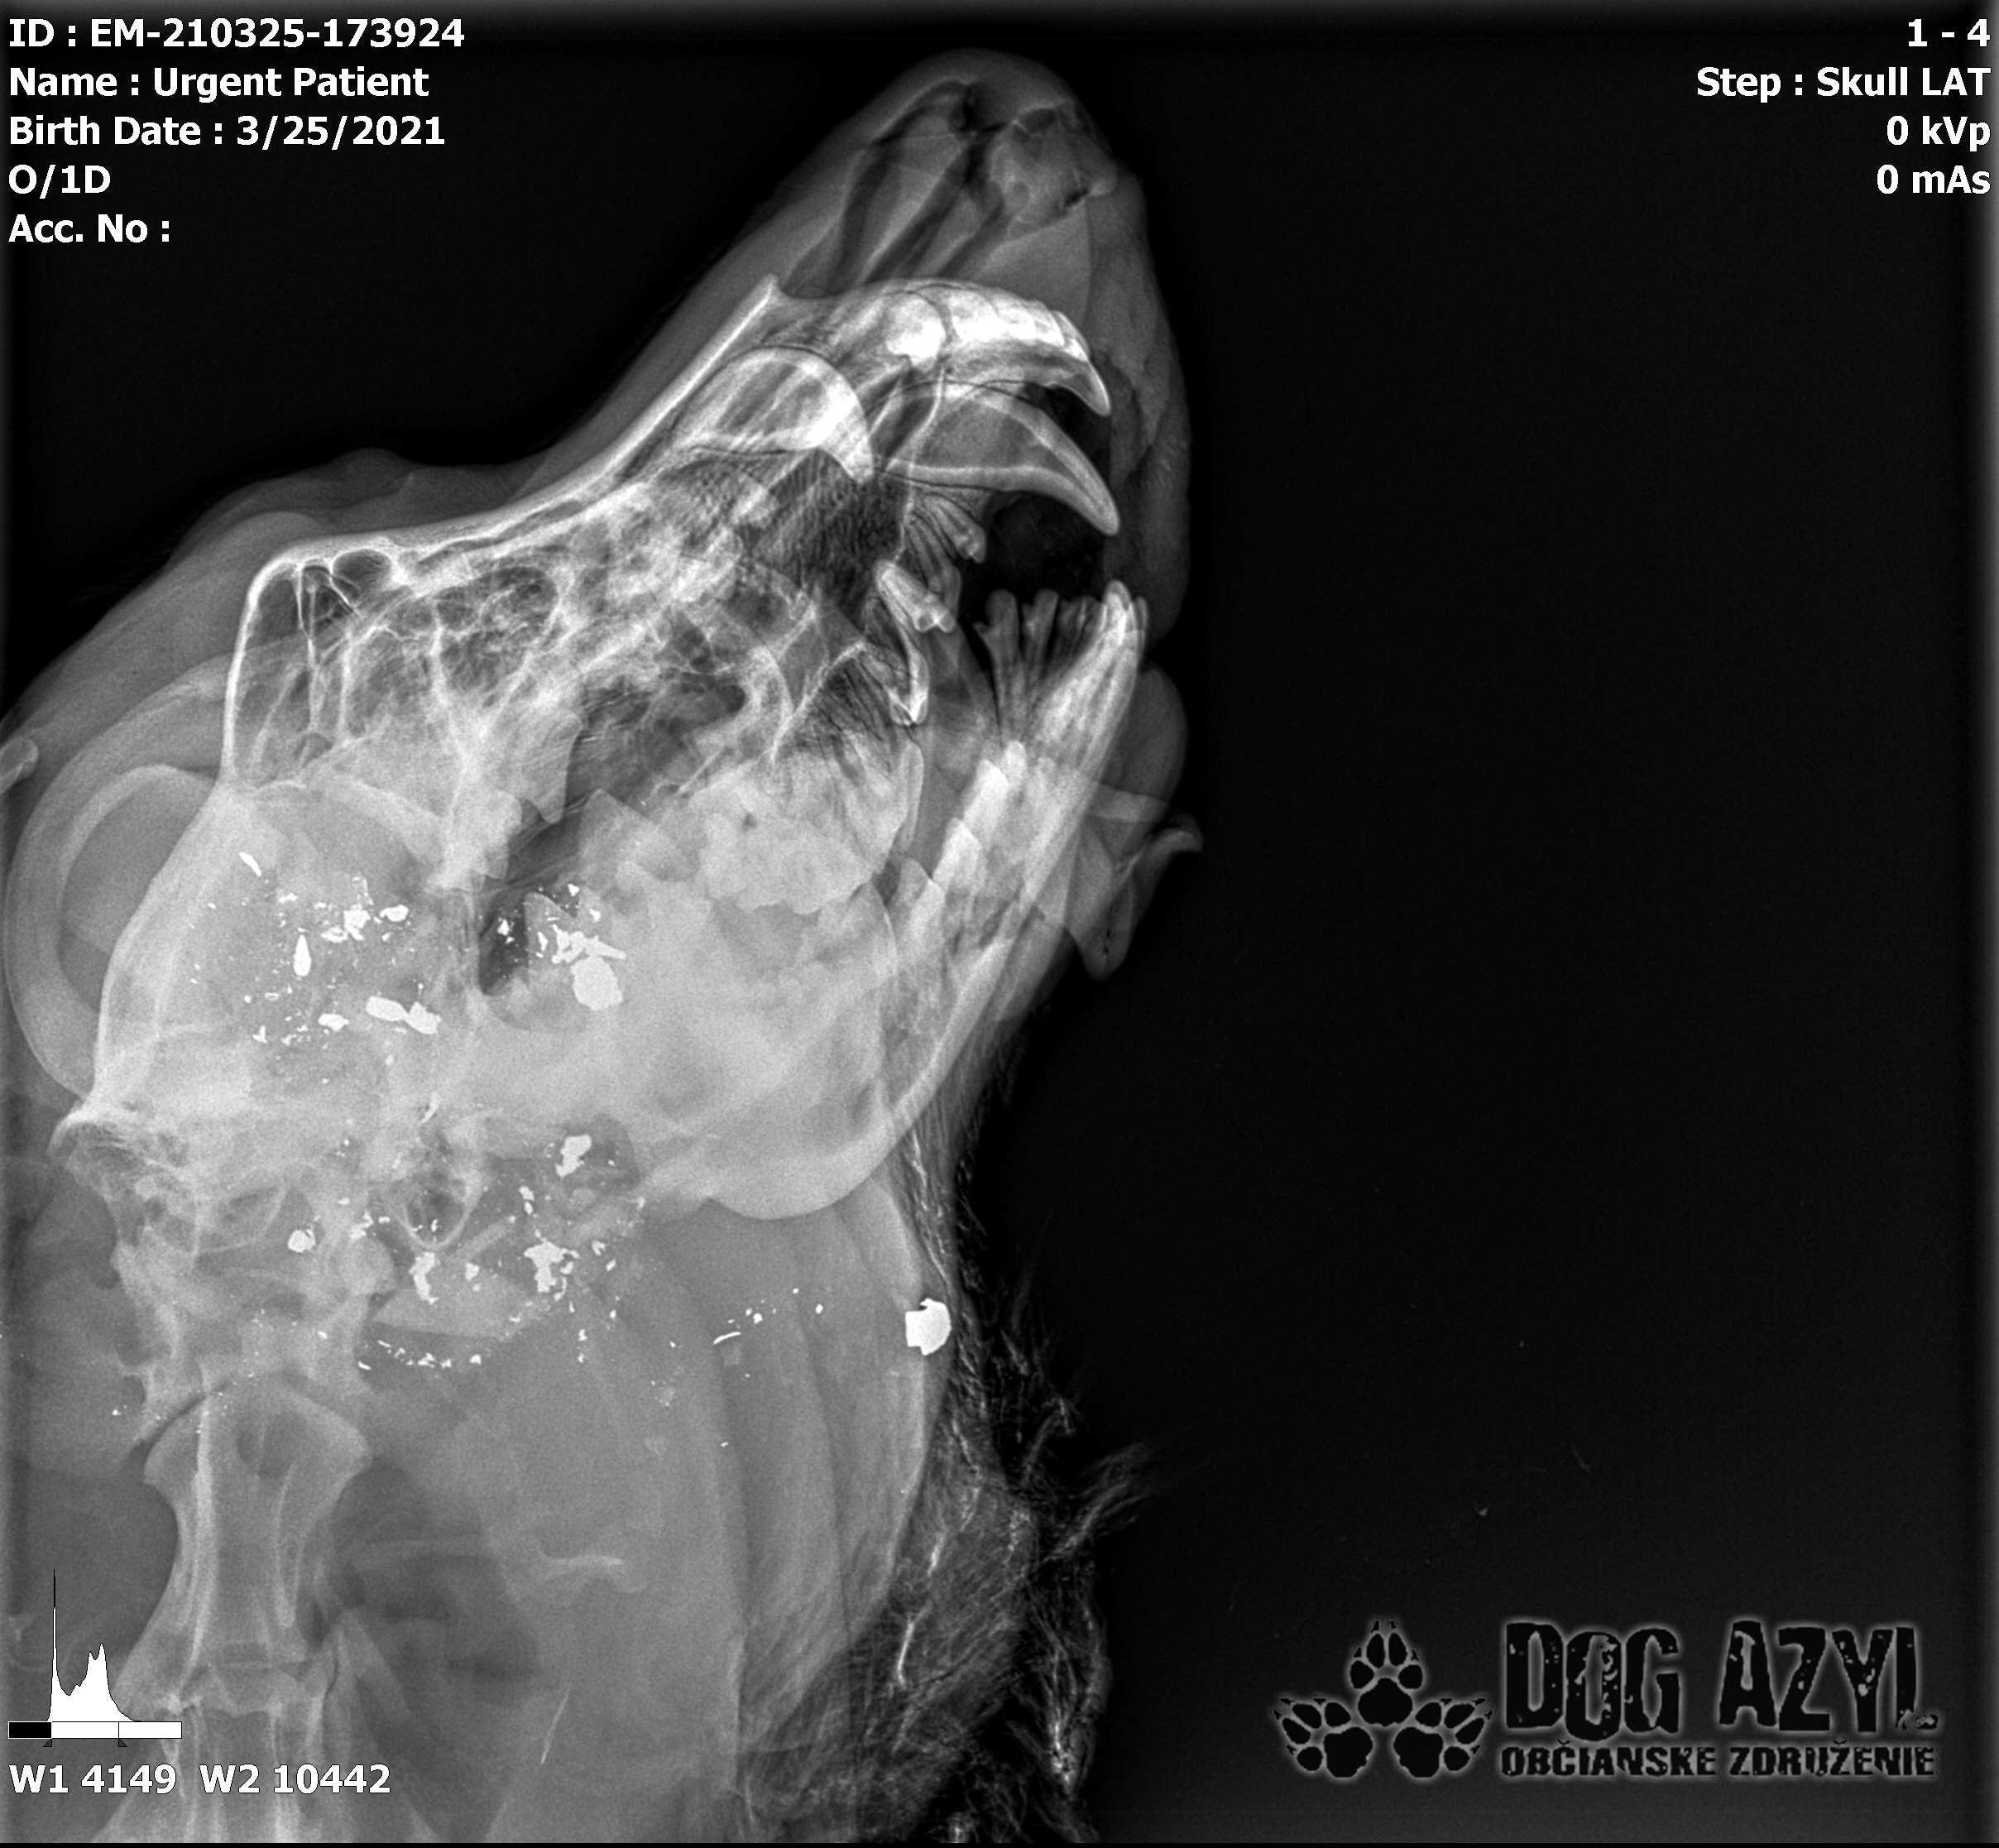

Strela zasiahla Barisa v oblasti lícnej kosti, ktorá mu rozdrvila sánku a následne putovala cez krk až po krčnú chrbticu. Úlomky z guľky (neviem ako sa to odborne volá) sa roztrieštili na "milión" kusov počas svojej cesty. Tieto úlomky sú všade (ako vidieť aj na RTG). Jeden (alebo niekoľko týchto úlomkov) sa dostali až po miechu, ale našťastie ju neprerazili. Toto spôsobilo, že Baris citlivosť v nohách na ľavej strane sice má, ale má poškodenú motoriku. Tieto úlomky sa z oblasti stavcov, miechy aj krku dnes odstránili, ale Barisko z ďaleka nemá vyhraté. Miecha je totiž zakrvácaná (opäť sa ospravedlňujem za nepresnosť a laickosť) a to, že ako veľmi je poškodená, alebo či jeho slabosť bola spôsobená "iba opuchom" sa ukáže cca do 24 hodín. Ak Baris nedajbože do zajtra stratí citlivosť v nohách, tak.. žiaľ... Ale! ak citlivosť zostane, prípadne nastane aj zlepšenie, tak vzplanie plamienok ďalšej nádeje a bojujeme ďalej!